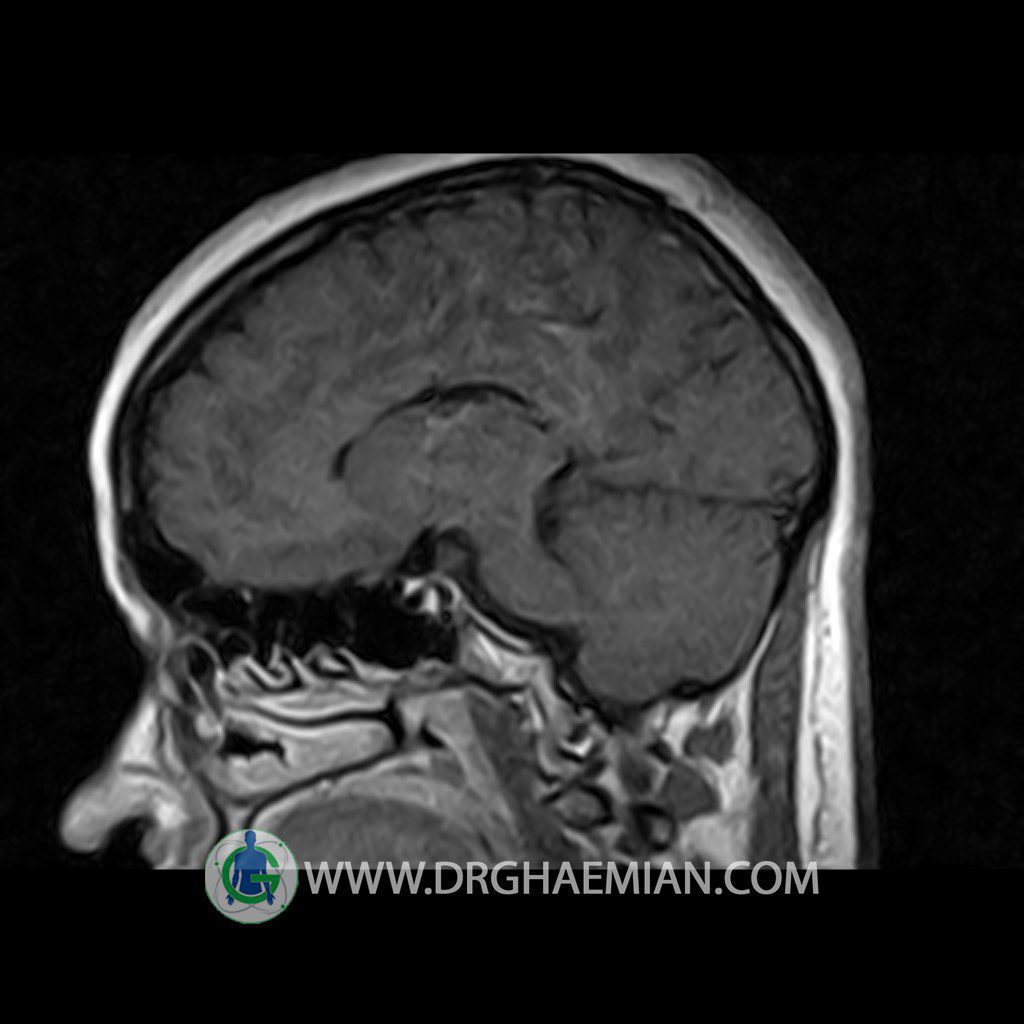

ام آر آی هیپوفیز یک روش تصویر برداری است که از غده هیپوفیز (غده ایی کوچک در مغز که هرومون ها و دیگر غدد بدن را کنترل می کند) و ناحیه های پیرامونش در مغز تصاویری ایجاد می کند. در این کیس سلای نسبتا خالی در ناحیه هیپوفیز بیمار مشاهده می شود.

Technique: Axial , coronal T1 , Axial , coronal , sagittal T2 , Axial, coronal T1 post Gd & 64 dynamic thin coronal slices.

– Extension of suprasella cistern to sella with thin pituitary gland in floor of sella ( partial empty sella )

is seen